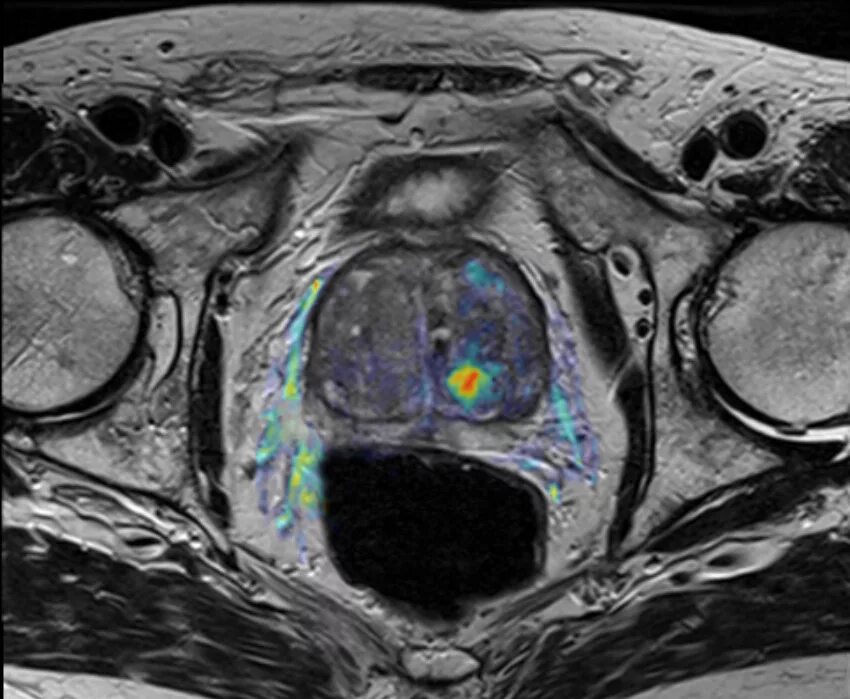

Простатит везикулит